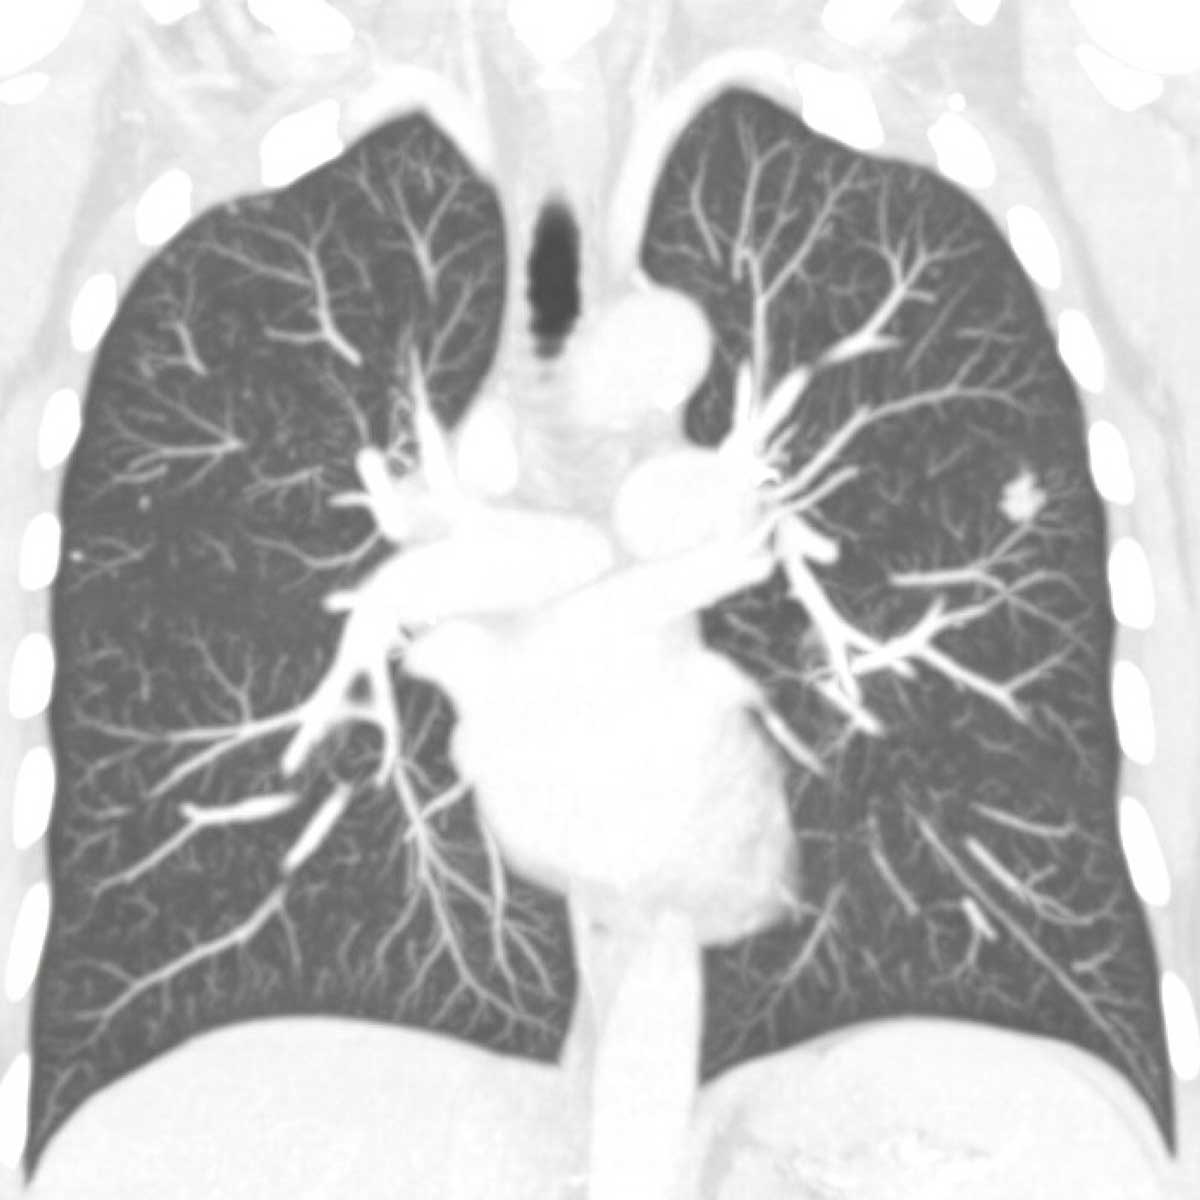

An x-ray scan of Laura Dehlendorf’s lungs after her procedure

A post-surgery scan showing the same lung with no signs of the tumor.